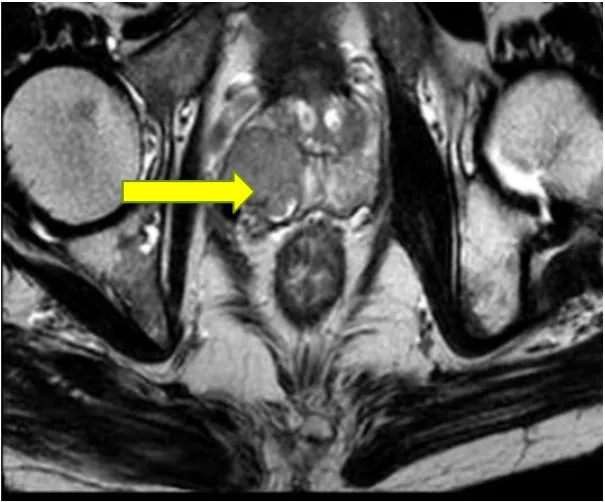

前列腺MRI(2024-11-28)

前列腺右侧周围带可疑肿瘤,与右侧肛提肌分界欠清、前列腺增生伴钙化、右侧股骨头异常信号灶,考虑退行性改变。

前列腺大小约为4.9cm×4.9cm×3.5cm,形态异常,右侧包膜欠光整,右侧周围带见团块状异常信号灶,T2WI等低信号,T1WI低信号,DWI明显增高,边界欠清,长径约为3.9cm,与右侧肛提肌分界不清,略受推挤向外侧移位。

左侧周围带信号不均匀减低,中央带及移行带信号不均,其内见斑片状极低信号影。双侧精囊腺对称,充盈欠佳。膀胱充盈欠佳,其内未见异常信号灶。直肠周围脂肪间隙未见异常。扫描野内未见明显肿大淋巴结。扫描野内右侧股骨头内见斑片状异常信号灶。

1. 考虑前列腺右侧周围带肿瘤,与右侧肛提肌分界欠清。

2. 前列腺增生,伴钙化。

3. 右侧股骨头异常信号灶,考虑退行性改变。